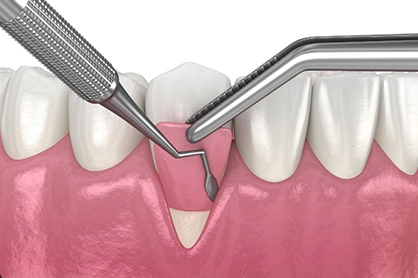

- Minimally Invasive: Our EXPERIENCE and METHOD give our patients faster RECOVERY time.

- Minimal Invasive Surgery